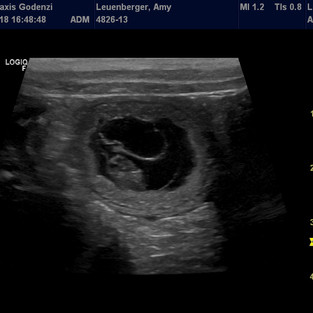

Wir waren heute mit Amy für eine Ultraschall-Kontrolle beim Tierarzt und er ist zu unserer grossen Freude fündig geworden! Wir konnten etliche Fruchtblasen mit laut TA gesundem Inhalt erkennen. Der Geburtstermin sollte zwischen dem 15. und 20. August 2018 liegen, wir sind sehr gespannt.